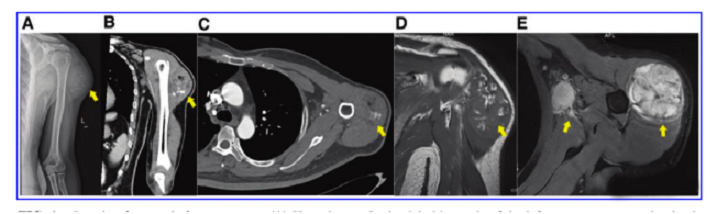

接受iPS细胞治疗患者的畸胎瘤。(A) 在左上臂的三角肌中,观察到一个圆形的混合密度肿块,边界不清,为9.6±5.2cm。(B) CT冠状扫描显示三角肌内有一圆形混合密度肿块,边界不清。(C)增强CT轴向扫描显示不均匀和中度强化。(D)MRI T1W以等信号为主,有不规则的高低信号区。(E) T2W也显示高信号和斑片状低信号区,左腋窝有多个淋巴结肿大。